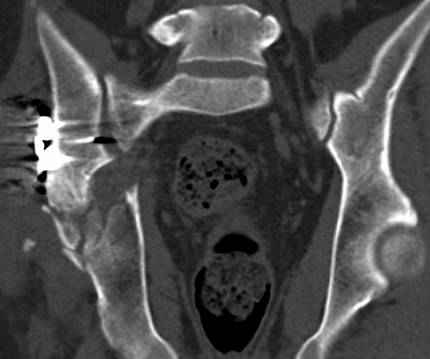

к таковым себя не причисляю, но...обычное дело для нашей страны - выкладывать 3D и не показывать стандартные проекции Judet. Дигност представляет те ракурсы, которые по-его мнению наиболее информативны, более того комп сам достраивает какие-то мелкие повреждения по 3D по своему усмотрению. По данной реконструкции можно предполагать высокий двухколонный перелом с оскольчатыми передней и задней колоннами, оскольчатую высокую переднюю колонну с задним полупоперечником или одно из перечисленных с вовлечение КПС. У меня впечатление за второй вариант, но нужно обследовать нормально - проекции, сканы.

высылаю дополнительно сканы.

По отдельным срезам и тем более по реконструкции трудно судить о сращении крыла и задней колонны с осевым скелетом.

Поэтому хотелось бы дообследовать больного (разумеется включив стандартные проеции judet,и срезы показывающие сращение)

Хорошо бы на рентгенограммы взглянуть и побольше срезов по своду. С каким отломком головка контактирует и как ее состояние.

Все выступающие коллеги высказались насчет необходимости стандартных снимков по Judet, потому что для определения тактики лечения переломов вертлужной впадины 3Д снимки малоинформативны.

Из того минимума, что представлено, мне кажется, мы имеем дело с двухколонным переломом вертлужной впадины. Обычно медиальный (центральный) "вывих" головки встречаются в сложных двухколонных переломах со смещением.